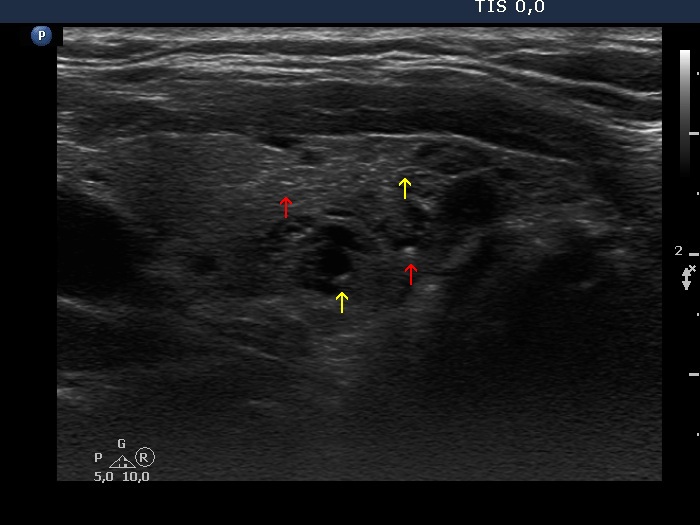

Consecutive patients with the final diagnosis of Hashimoto's thyroiditis - case 38 (1617) (ultrasonographic picture 6b)

Left lobe, another longitudinal view. Beside relatively pale echogenic lines (yellow arrows), there are brighter lines, as well. It means that the similarly bright granules are very likely also presentations of connective tissue.